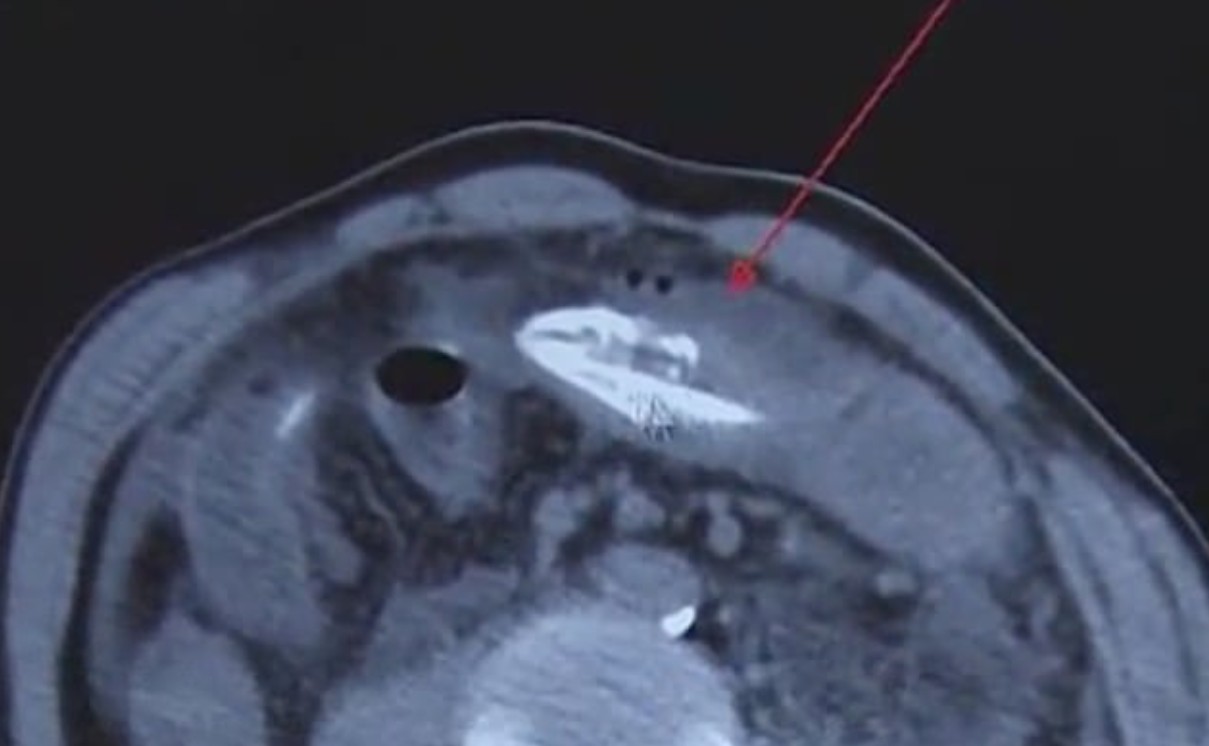

Μπροστά σε ένα απίστευτο περιστατικό βρέθηκαν… οι γιατροί σε νοσοκομείο της Κίνας όταν εμφανίστηκε άνδρας, ο οποίος είχε βάλει ένα τεράστιο χέλι στον πρωκτό του, προκειμένου να «ανακουφιστεί» από τη δυσκοιλιότητα που τον ταλαιπωρούσε.

Σύμφωνα με την dailymail.co.uk πρόκειται για χέλι, μήκους σχεδόν 20 εκατοστών, το οποίο όχι μόνο ήταν ακόμα ακόμα ζωντανό, αλλά κατάφερε να φτάσει μέχρι την κοιλιά του άτυχου άνδρα, ο οποίος λίγο έλειψε να βρει τραγικό θάνατο, αναζητώντας εναλλακτικές ιατρικές θεραπείες.

Σύμφωνα επίσης με τους γιατρούς, το χέλι, το οποίο εξερεύνησε το πιο παράξενο και αφιλόξενο μέρος που έχει βρεθεί ποτέ, δάγκωσε το έντερο του Κινέζου, ο οποίος ισχυρίζεται ότι η θεραπεία που επέλεξε βασίζεται σε ένα παλιό παραδοσιακό γιατροσόφι για την καταπολέμηση των προβλημάτων του παχέος εντέρου.

Σύμφωνα πάντα με το δημοσίευμα, οι γιατροί αφαίρεσαν με χειρουργική επέμβαση το μεγάλο χέλι, το οποίο παρά τις αντίξοες συνθήκες στις οποίες βρέθηκε… επέζησε.